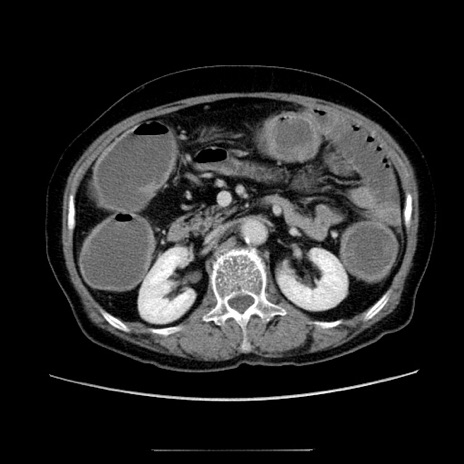

症例5(横断像)

【症例】70歳代女性

【主訴】お腹が張る

【現病歴】1週間くらい前から腹部膨満の自覚あり。昨日夜から増悪したため、本日救急外来受診。

【身体所見】意識清明、BT 36.5℃、BP 165/106mmHg、HR 80bpm、SpO2 98%、腹部:膨満、軟、自発痛・圧痛なし、触診にて不快感あり、腸蠕動音:減弱

【データ】WBC 12600、CRP 1.04